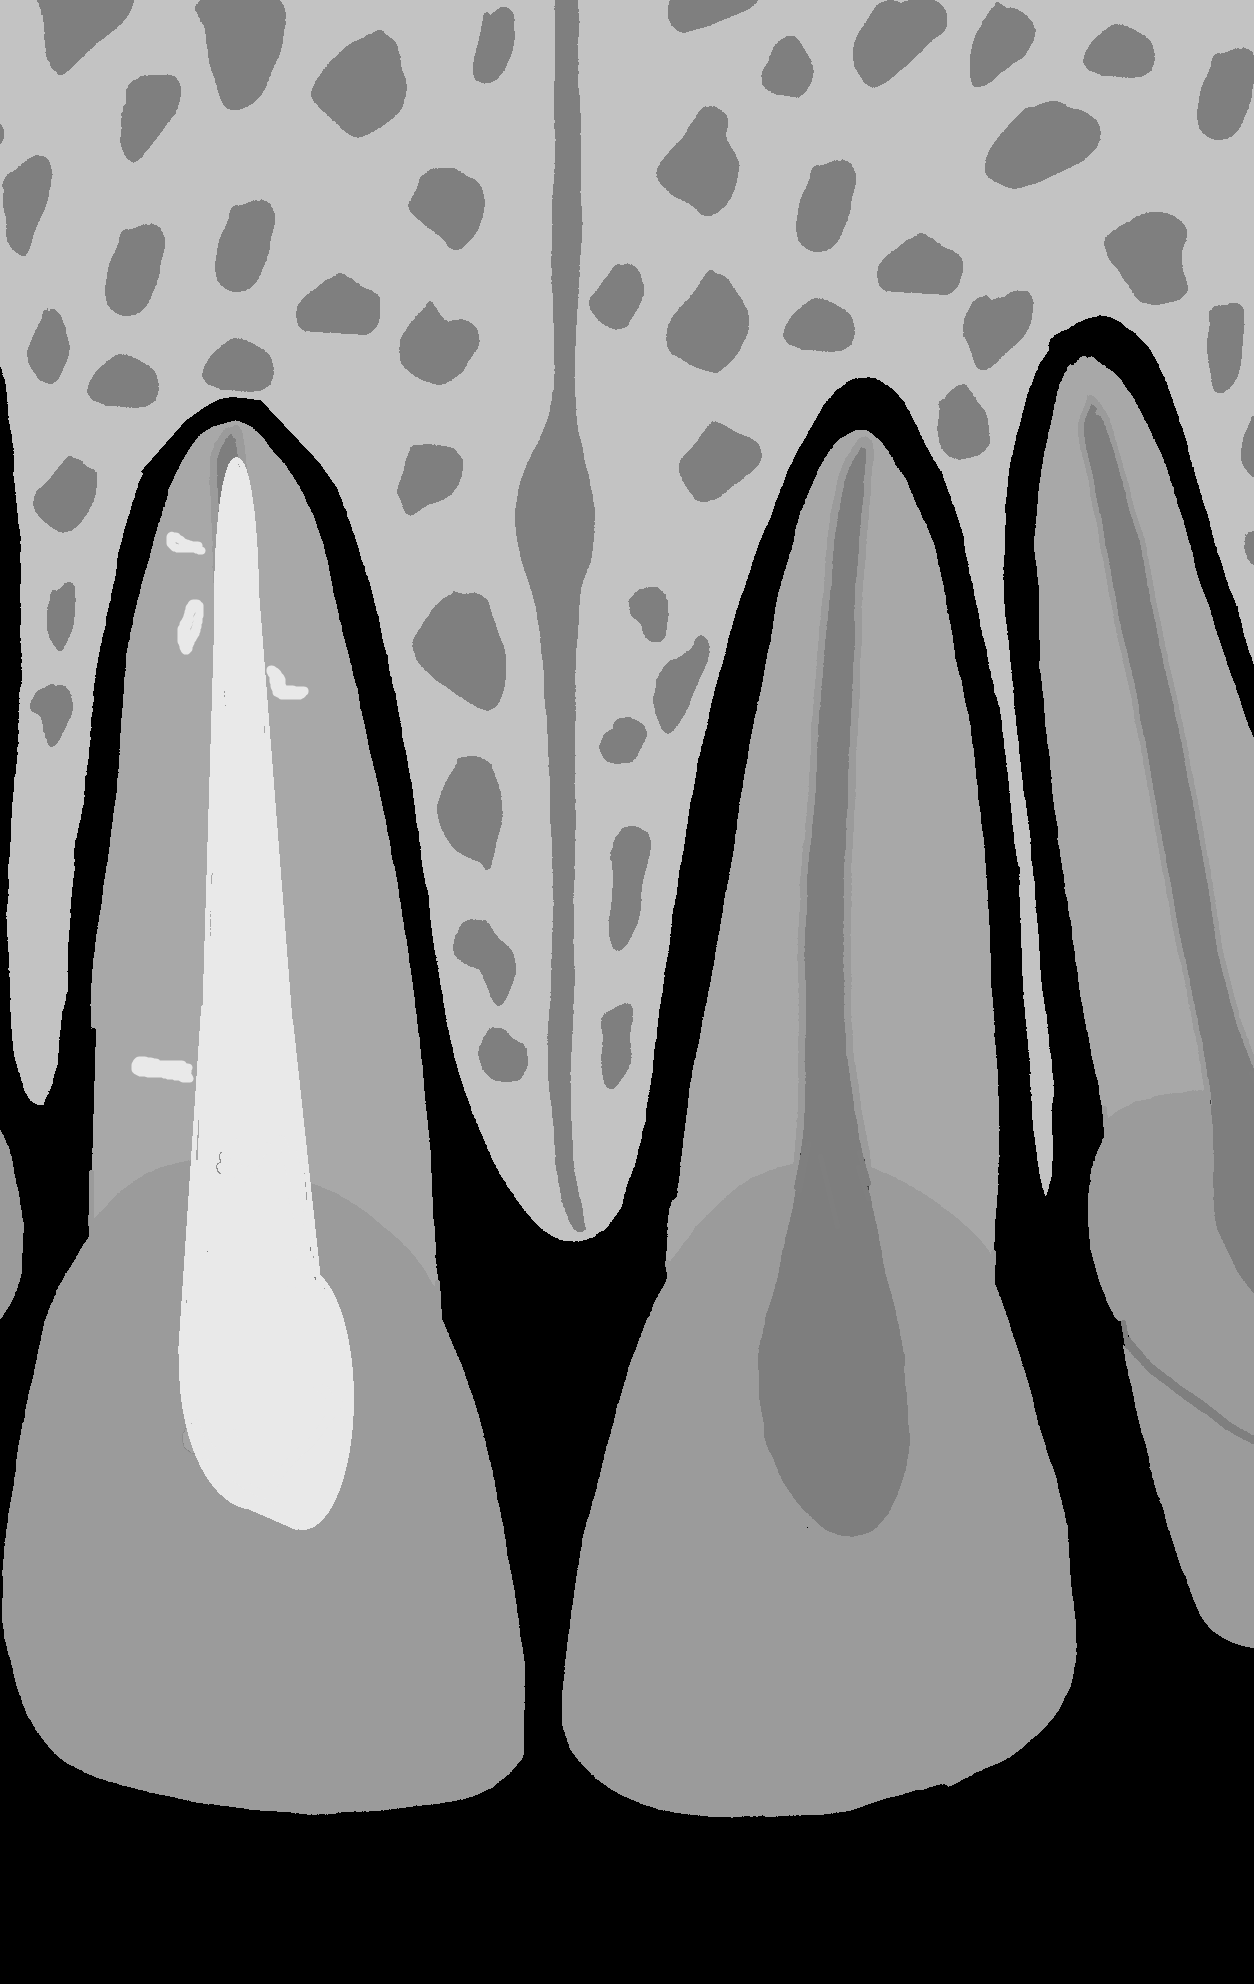

Na kontrolnym zdjęciu rentgenowskiemu wykonanym po wypełnieniu kanału nie rozpoznał perforacji, choć należy przyznać, iż było to dość trudne. Wynikało z faktu, iż operator wypreparował sztuczny kanał w osi właściwego kanału korzeniowego i w związku z tym po jego wypełnieniu obraz materiału umieszczony w kanale perforacyjnym nałożył się na obraz kanału naturalnego (ryc. 1A). Oczywiście doświadczony diagnosta prawdopodobnie zauważyłby niewielkie ilości uszczelniacza poza zarysem kanału i w celu pogłębienia diagnostyki wykonałby zdjęcie rentgenowskie w projekcji skośnej (ryc. 1B), która uwidoczniłaby perforację, lub zdecydowałby się na wykonanie badania CBCT, które wnosi zdecydowanie więcej informacji niż zdjęcie zębowe (ryc. 2A, B). Taką decyzję podjął zresztą endodonta, który wykonał CBCT. Badanie wykazało wypełniony materiałem sztuczny kanał perforacyjny położny dowargowo od nietkniętego kanału naturalnego. Ponieważ wynik badania wrażliwości miazgi prądem faradycznym nie różnił się od zębów sąsiednich, endodonta poinformował pacjenta, że ponowne leczenie może ograniczyć się wyłącznie do usunięcia gutaperki i zamknięcia perforacji. Ostatecznie jednak nie udało się uniknąć leczenia endodontycznego, a ze względu na trudności usunięcia gutaperki od strony jamy zęba wykonano zabieg chirurgiczny i usunięto ją od zewnątrz.

Ryc. 1. Możliwości diagnostyczne wewnątrzustnego zdjęcia zębowego. A. Zdjęcie wykonane w projekcji ortoradialnej. Obraz radiologiczny ćwieka gutaperkowego nakłada się na obraz światła kanału korzeniowego, co może sugerować prawidłowo wykonane leczenie endodontyczne. Wątpliwości budzą niewielkie ilości uszczelniacza poza zarysem wypełnienia. B. Zdjęcie wykonane w projekcji skośnej, które uwidacznia kanał perforacyjny wypełniony materiałem oraz nietknięty kanał właściwy.